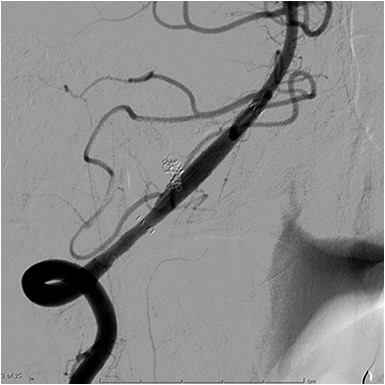

A 48-year-old man was admitted to our hospital because of loss of consciousness after a sudden nuchal pain. Brain computed tomography (CT) showed diffuse SAH (Fig. 1A). The following CT angiogram showed a fusiform aneurysm at the right vertebral artery with contralateral hypoplasia (Fig. 1B). The endovascular procedure was performed under general anesthesia. The patient received a loading dose of 200 mg of aspirin and 300 mg of clopidogrel via a nasogastric tube. A preoperative angiogram showed VAD with a blister at the pseudolumen (Fig. 2A). Initially, a stent (Enterprise, 4.5 mm × 37 mm; Codman, Raynham, MA, USA) was deployed from the basilar artery to the right vertebral artery. A second stent (Enterprise2, 4.0 mm × 30 mm) then overlapped the first stent, covering the pseudolumen (Fig. 2B). Coiling was performed from a microcatheter (Excelsior SL-10/45; Boston Scientific, Fremont, CA, USA), which was jailed in the pseudolumen. After the first coil perforated the blister, a balloon catheter (Scepter C, 4.0 mm × 15 mm; Microvention, Tustin, CA, USA), which was exchanged with a stent delivery catheter, was inflated in the stent. All five small platinum coils (Target nano, 2 mm × 4 cm and 1.5 mm × 2 cm; Stryker, Fremont, CA, USA) completely occluded the pseudolumen (Fig. 2C), and the right vertebral artery was preserved (Fig. 2D). Magnetic resonance imaging, which was obtained 3 weeks after the procedure, showed right cerebellar infarction without damage of the brainstem (Fig. 3). The patient recovered and returned to his former job after 2 weeks of intensive care and 3 months of rehabilitation therapy. An angiogram, which was obtained 6 months after procedure, showed no recurrence of VAD (Fig. 4).

Angiogram obtained 6 months after the procedure shows no recurrence of vertebral artery dissection.